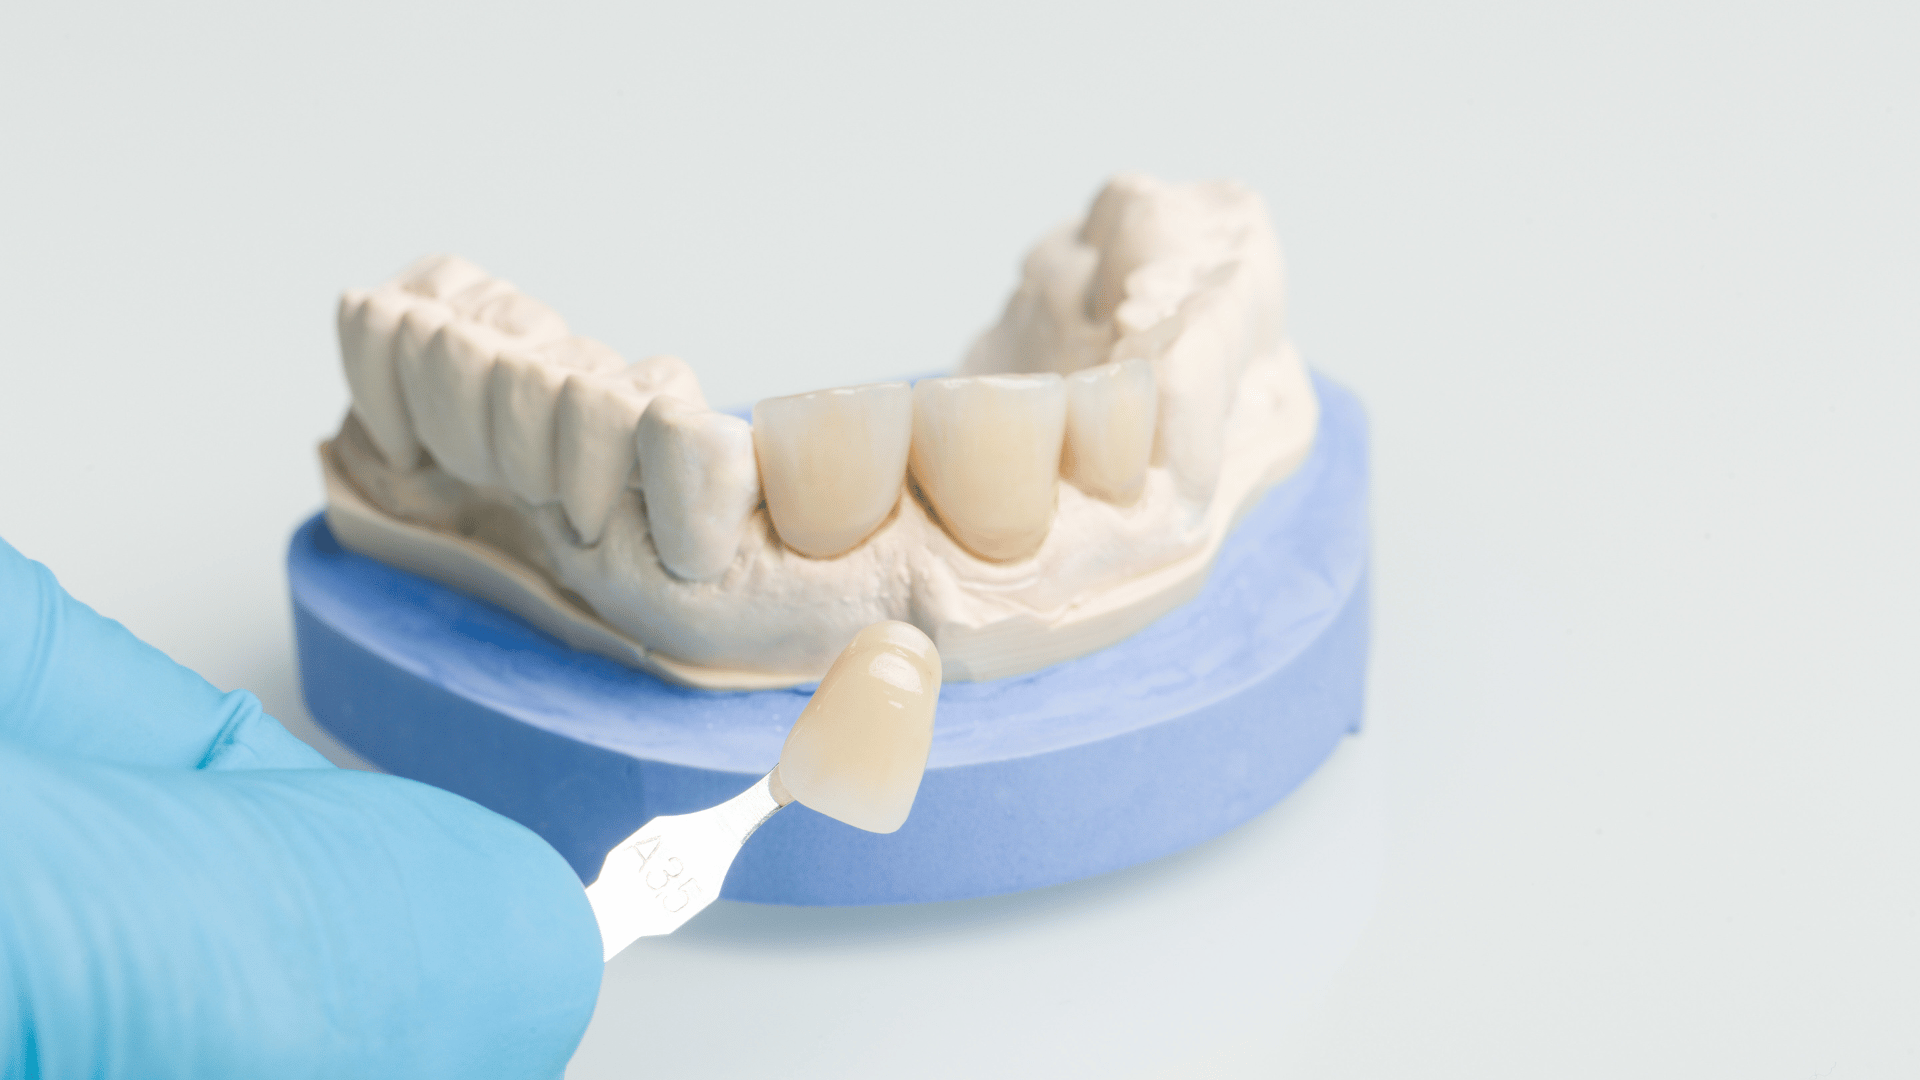

Die CEREC-Technologie ermöglicht es uns, Zahnkronen aus hochwertigen Materialien direkt in unserer Praxis herzustellen.

Erleben Sie die Zukunft der Zahnmedizin mit unserer CEREC-Technologie! Bei DentalCare Plus bieten wir Ihnen die Möglichkeit, hochwertige Zahnkronen in nur einer Sitzung anzufertigen. Durch modernste CAD/CAM-Technologie erstellen wir präzise, passgenaue Kronen, die nicht nur funktional, sondern auch ästhetisch ansprechend sind.